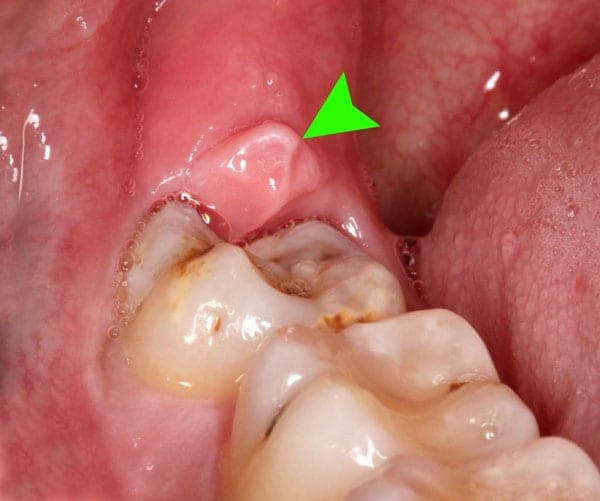

Đây là biến chứng thường gặp nhất khi người bệnh có răng khôn nhưng không xử lý sớm. Tình trạng lợi trùm xảy ra khiến thức ăn bị bám lại, kẽ hỡ giữa phần lợi và răng không được làm sạch triệt để khiến hiện tượng nhiễm trùng xảy ra. Nếu bị viêm lợi trùm, người bệnh cần phải điều trị nội nha trong khoảng một tuần để hiện tượng viêm ổn định mới có thể nhổ răng khôn.

Viêm lợi trùm răng khôn là biến chứng thường xảy ra nếu không nhổ răng khôn sớm